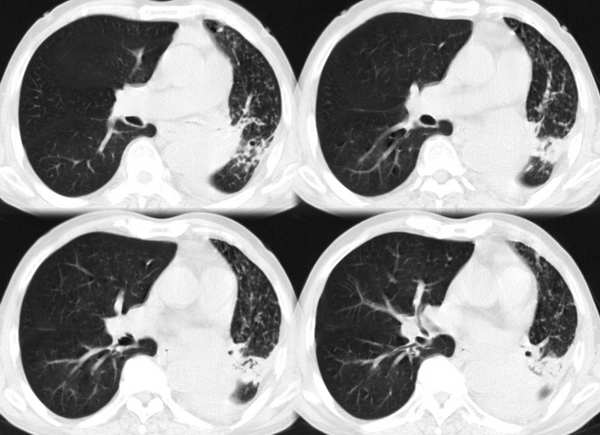

m67y外院ct诊断肺ca,现来我科复查ct

左肺下叶支气管狭窄局部见肿块影左肺下叶不张,肺癌应该没问题吧

典型中央型肺ca

左主支气管变窄,左下叶部分不张,考虑肺癌可能性大

考虑左下肺中央型肺癌并肺不张,建议支气管镜检查。

肺癌半癌性淋巴管炎。